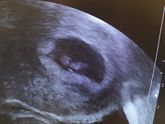

28 февраля 2020 10:19 Только 9 недель, а меня че то начинает потихоньку пропускать сонливость и приходит бодрость духа. Переживаю, все ли нормально с малышом. Грудь всё такая же налитая и побаливает, периодическая тошнота остаётся, чувствительность на запахи тоже. У кого … Читать далее